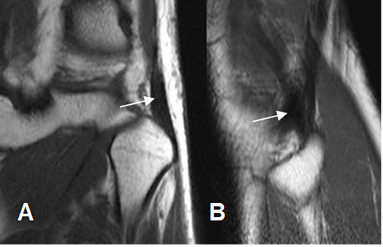

Fig 25. Fabela normal.

A: Rx lateral, B: RM sagital en T1 y C: RM coronal en T1. Fabela normal, en la parte posterior del cóndilo femoral externo.

Fig 26. Fabela normal.

A: RM sagital y B: RM coronal en T1. Ligamento fabelofibular normal.